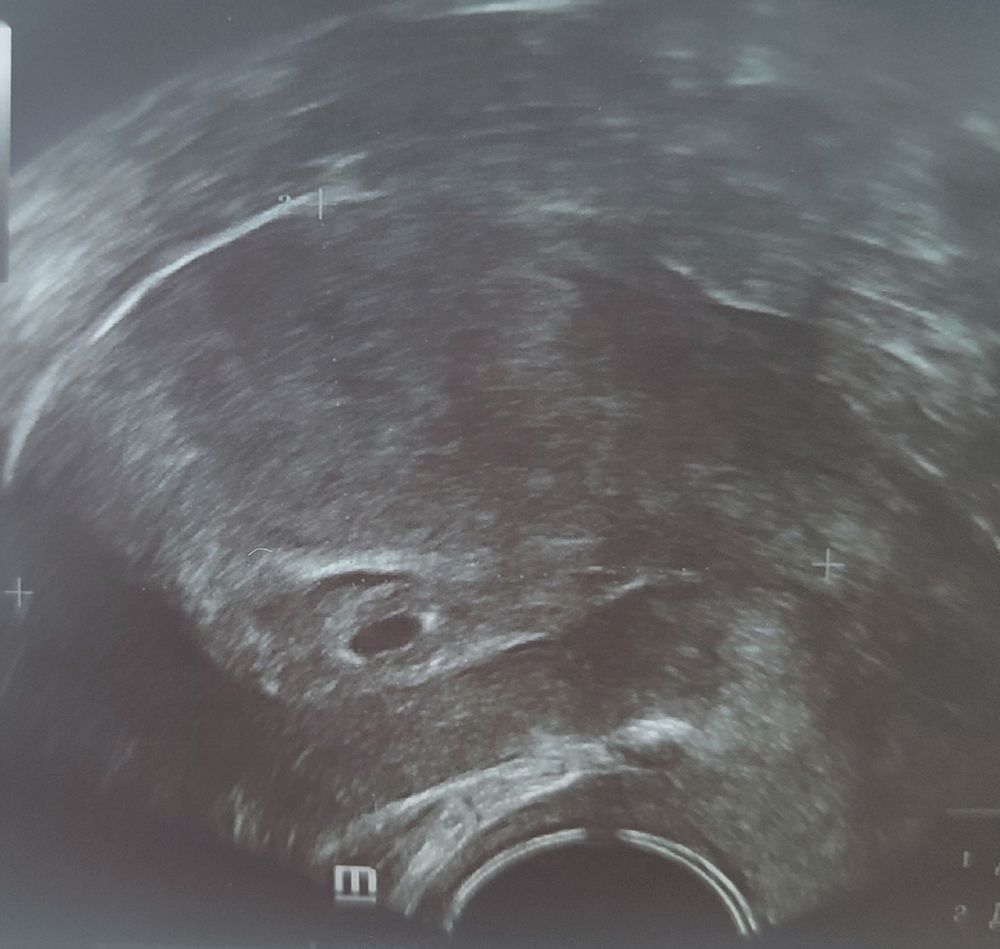

15 ДПП. УЗИ.

Промежуточные итоги: плодное яйцо в матке, СВД 6 мм. Больше пока ничего, но это и понятно. Гематома над плодным яйцом 8 на 3... Врач сказала не паниковать, но, понятно, всяческий покой. По моей просьбе (точнее, после вопросов) добавили масляный прогестерон. 6 числа всё-таки, если все будет хорошо, сгоняю ещё раз к своему врачу посмотреть и на эту гематому, и, быть может, уже на сердечко.

Жёлтое тело уменьшилось, всего 15 мм.

Наше второе фото). Первое было сразу после переноса.

Верю в чудеса, я сейчас смотрела лекцию гинекологических узистов, так вот они полоску анэхогенную, образующую симптом второго кольца, вообще называют отличительным признаком этого срока беременности, а не гематомой или чем-то таким. У меня выделений нет (вчера было прям меньше миллиметра), думаю: может, это не гематома вовсе? Смущает, что так далеко от плодного яйца на картинке как будто.

Хотя я уже, конечно, начиталась, что гематома, расположенная над плодным яйцом, имеет худший прогноз и тд. Ну и размер гематомы больше размера плодного яйца не радует.